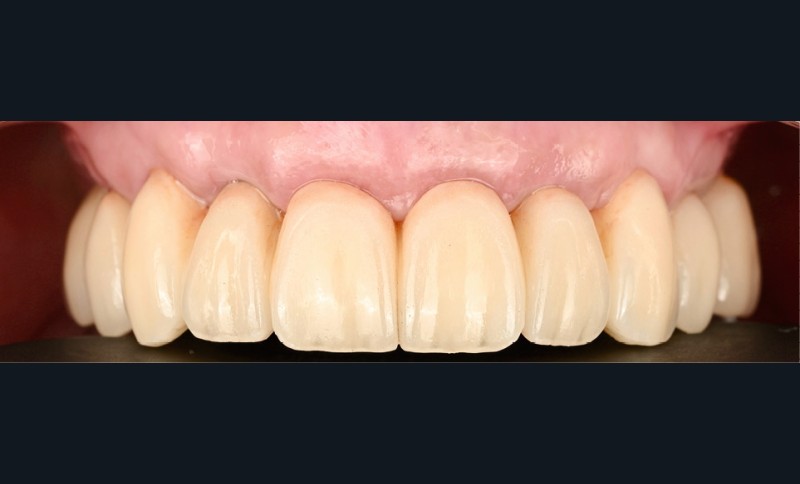

Elle est réalisée en zircone monolithique usinée puis stratifiée manuellement (fig. 9). Dans cette approche hybride numérique-analogique, la CFAO assure la précision de la structure, tandis que la stratification manuelle apporte la personnalisation esthétique et la vitalité du rendu [4]. Le résultat illustre la convergence entre précision technologique et sensibilité clinique (fig. 10).